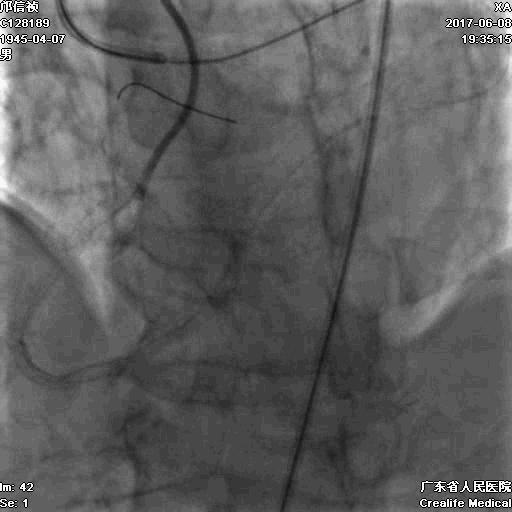

1.正向2.5*15mm球囊扩张,Reverse CART

2.Guidezilla延长导管辅助下,逆向导丝进入正向GC

1.更换RG3导丝

2.GC送入普通导丝,保护LM